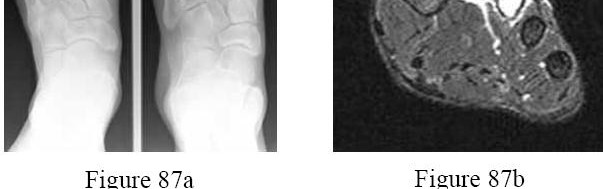

Question 7:

A 54-year-old male with long-standing diabetes presents with a swollen, warm, and erythematous left foot. Radiographs reveal fragmentation and periarticular debris at the tarsometatarsal joints. Which classification system is commonly used to stage the anatomical location of this disease process?

Correct Answer: Brodsky classification

Explanation:

The Brodsky classification describes the anatomic location of Charcot arthropathy. Type 1 is the tarsometatarsal (Lisfranc) joint, which is the most common. Type 2 involves the Chopart/subtalar joints. Type 3A involves the ankle (tibiotalar), and Type 3B involves the calcaneal tuberosity. The Eichenholtz classification describes the clinical and radiographic progression (development, coalescence, consolidation).